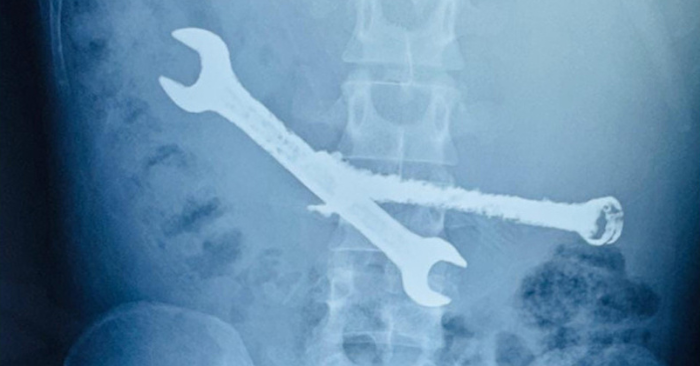

Các bác sĩ tại thành phố Jaipur; bang Rajasthan (Ấn Độ), vừa thực hiện ca phẫu thuật khẩn cấp, lấy ra hai chiếc cờ lê bằng sắt cùng 7 bàn chải đánh răng găm chặt trong dạ dày một nam bệnh nhân 26 tuổi. Đây được xem là trường hợp y khoa hiếm gặp; tiềm ẩn nguy cơ đe dọa tính mạng nếu không can thiệp kịp thời.

Bác sĩ Tanmay Pareek, chuyên gia tiêu hóa trực tiếp điều trị; cho biết kết quả chẩn đoán hình ảnh ban đầu khiến cả êkíp bất ngờ. Dạ dày bệnh nhân chứa nhiều vật thể cứng, kích thước lớn, hình dạng dị thường, chiếm gần như toàn bộ khoang tiêu hóa; trông giống một “thùng chứa phế liệu”.

Sau hơn hai giờ căng thẳng; kíp mổ lần lượt lấy ra hai chiếc cờ lê bằng sắt và 7 bàn chải đánh răng còn nguyên vẹn. Các dị vật được xác định đã tồn tại trong dạ dày người bệnh trong thời gian dài; gây viêm loét và tổn thương nghiêm trọng cơ quan tiêu hóa.